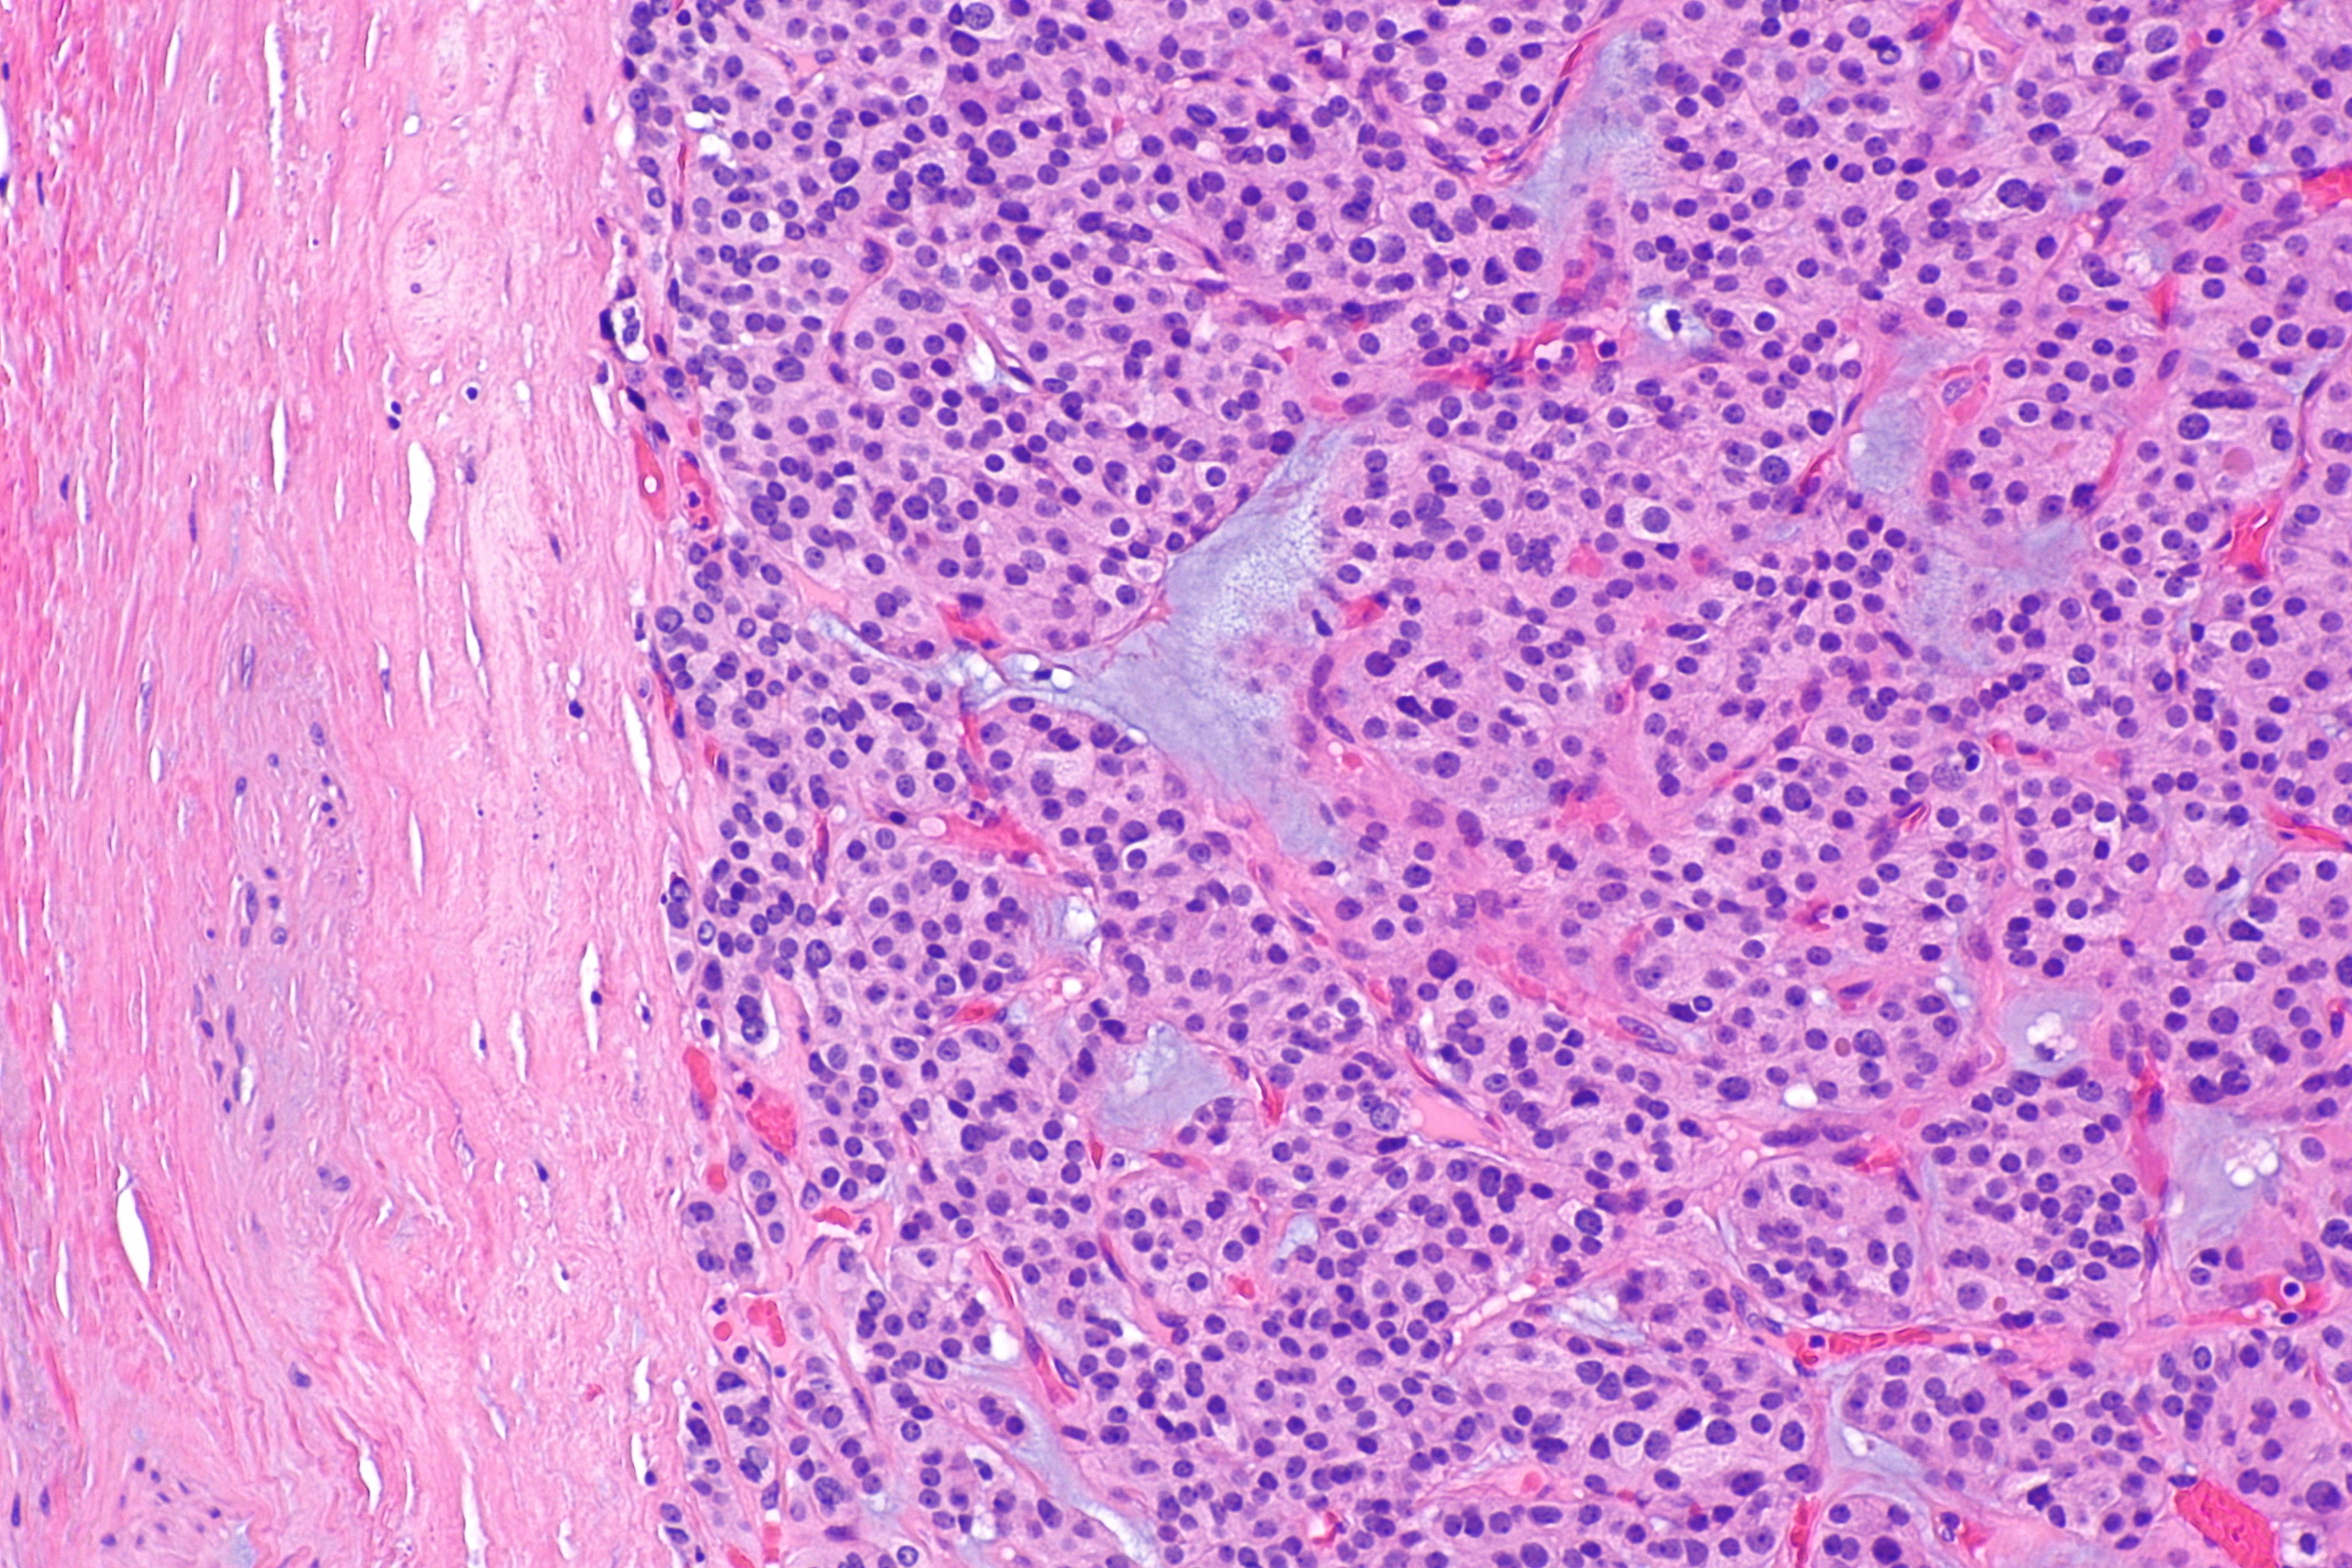

Базофильная аденома

Базофильная аденома 110 фотографий